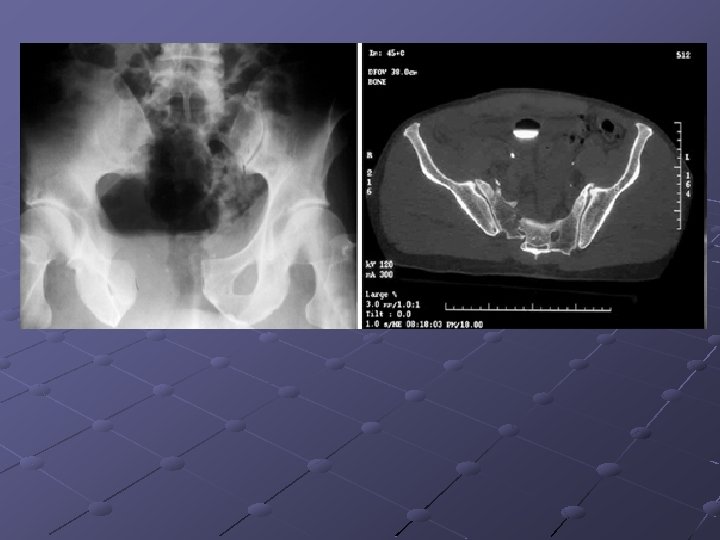

Imaging Studies